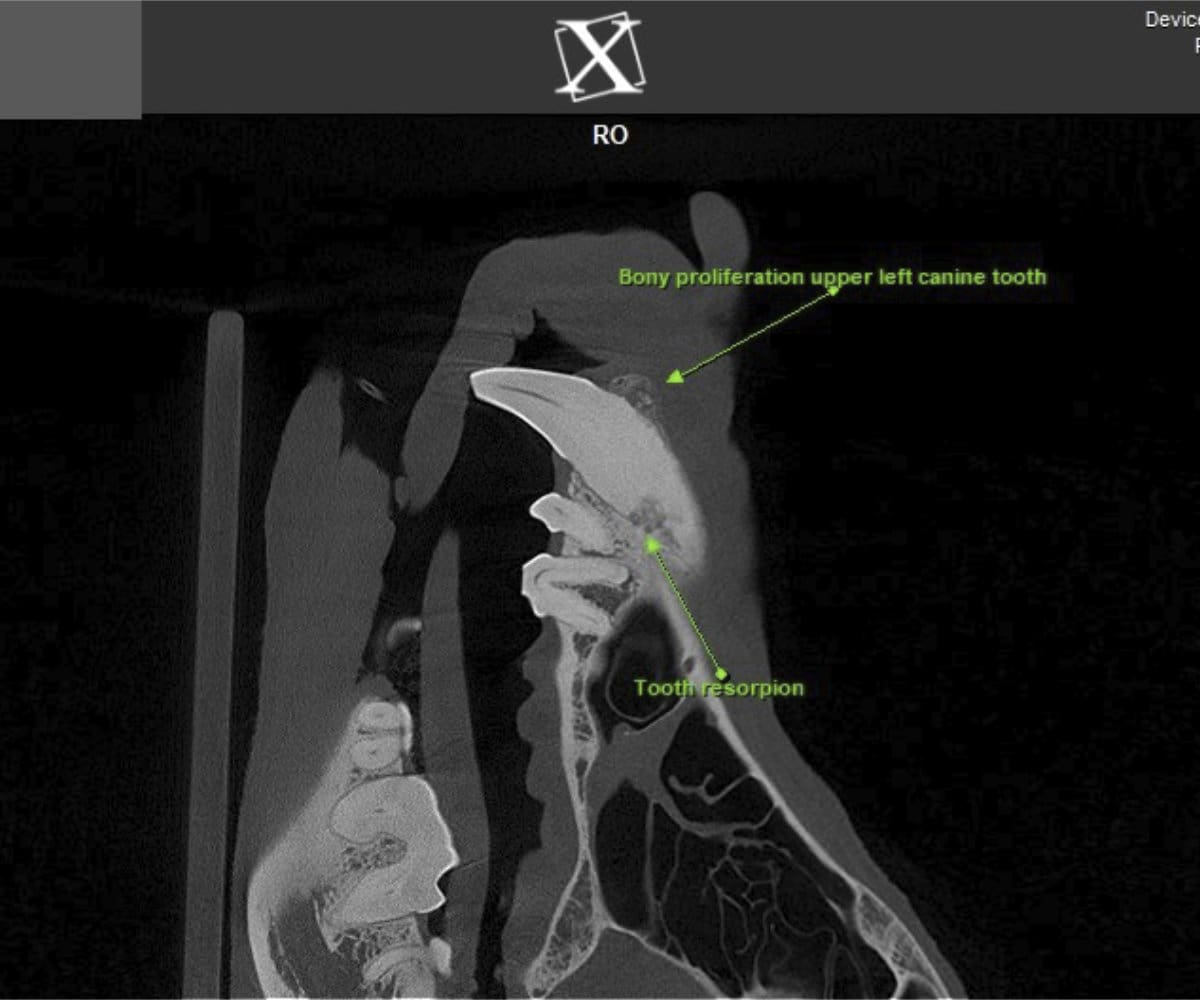

In addressing these limitations, CBCT emerges as a pivotal advancement. Conducting a CBCT scan on our patients is characterized by minimal time and effort, effectively reducing anesthesia duration. Moreover, this technology facilitates the generation of a comprehensive 3D reconstruction of the teeth and skull, surpassing the constraints of traditional radiographs. This innovative approach empowers our veterinary professionals to identify oral pathologies that may have been missed on traditional radiographs.

Cone beam CT technology provides veterinarians with 3-dimensional images in far greater detail than dental radiographs. CBCT scans significantly decrease the amount of time a patient spends under anesthesia compared to the time it takes to complete dental radiographs.

Our CBCT VetCAT unit is easily rolled up to our treatment table and takes only 40 seconds to complete a scan. It has proven to be invaluable in the diagnosis and treatment planning for pets with periodontal, endodontic and cancerous disease conditions. It is also indispensable in the evaluating our trauma cases with jaw fractures.